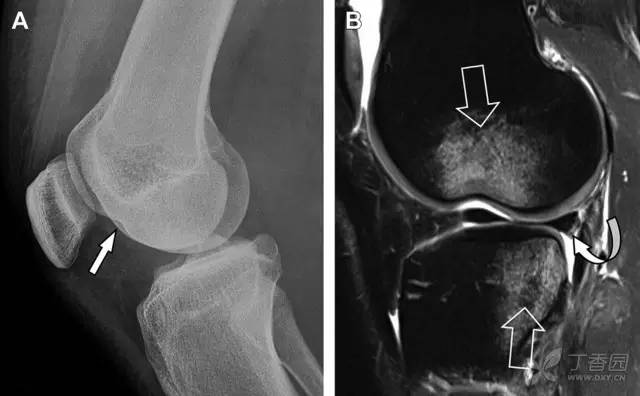

膝关节撕脱骨折和压缩骨折常伴发于韧带损伤,若想准确诊断,在了解这些骨折高发部位的同时,还需仔细认真地阅片,否则有些骨折就被漏诊了。

前交叉韧带撕脱骨折常发生在胫骨髁间嵴(图 1)。这种骨折在青少年中常见,但在成年人中也并不像大家想象的那么少见。

图 1 摩托车事故患者前交叉韧带撕脱性骨折

A 正位片示胫骨髁间嵴底部骨折(箭头),关注别把这个骨折碎片错认为关节内结构。B 侧位片示胫骨上方可见一细长型骨折碎片(椭圆)。C MRI 矢状位 T2 加权像示前交叉韧带附着于撕脱的骨折碎片上(箭头),关注周围存在骨髓水肿和积脂血征(空箭头)。

图 2 扭伤后的股骨外侧髁凹陷征

A 侧位片示股骨外侧髁凹陷。B MRI 矢状位 T2 加权像示股骨外侧髁及胫骨后外侧骨挫伤(空箭头)。胫骨近端随着后交叉韧带撕裂发生移位,露出外侧半月板的后角(弧形箭头)。

胫骨后外侧小片骨皮质的压缩性骨折,可能是旋转移位损伤的唯一证据(图 3)。这种骨折在常规膝关节平片很难发现,若怀疑存在骨折,行下肢内旋斜位片检查可诊断。

图 3 胫骨后外侧碎片骨折

A 正位片示胫骨后外侧处可见一压缩骨折的小碎片(方框)。这是胫骨撞击股骨外侧髁旋转移位时所致。B 另一位患者的 MRI 矢状位 T1 加权像示胫骨后外侧骨折碎片(箭头)。

Segond 骨折是发生在胫骨平台外侧的垂直撕脱性骨折(图 4)。这种骨折在前后位 X 线片上显示最佳。

屈曲位时膝关节受到内旋*力暴**作用,导致皮质骨撕脱性骨折,这种骨折常发生在运动员身上。常引起股骨内髁和胫骨平台后内侧骨挫伤,75%~100% 的患者伴前交叉韧带断裂,33% 的患者伴外侧半月板损伤。

图 4 一位足球运动员的 Segond 骨折

A 正位片示关节线下方胫骨外侧皮质撕脱(箭头)。B MRI 冠状位 T1 加权像示附着于髂胫带的骨折碎片(空箭头)。